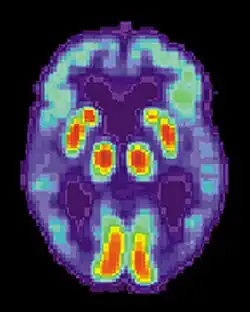

Los estudios de neuroimagen muestran que los pacientes con TOC se desempeñan considerablemente mejor en tareas de memoria procedimental debido a la notable sobreactivación de las estructuras cerebrales del estriado, principalmente del circuito frontoestriatal. Estos estudios sugieren que la memoria procedimental en pacientes de TOC se ve inusualmente mejorada durante las primeras fases de aprendizaje de la memoria procedimental.[51]